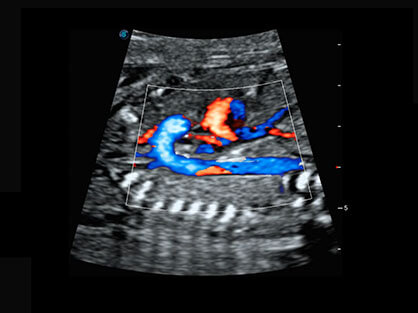

宽频带腹部凸阵探头和腹部容积探头、大角度腔内探头和腔内容积探头、独特的生殖专用曲柄探头,为妇产应用提供全面诊疗方案。

大角度腔内容积探头,可完整包络子宫及盆底结构,充分展示组织结构毗邻关系。